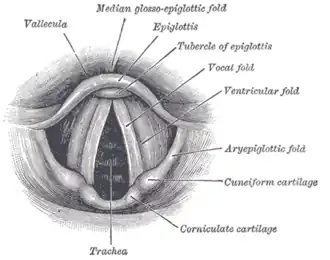

Entrée du larynx, vue postérieure.

Entrée du larynx, vue postérieure.